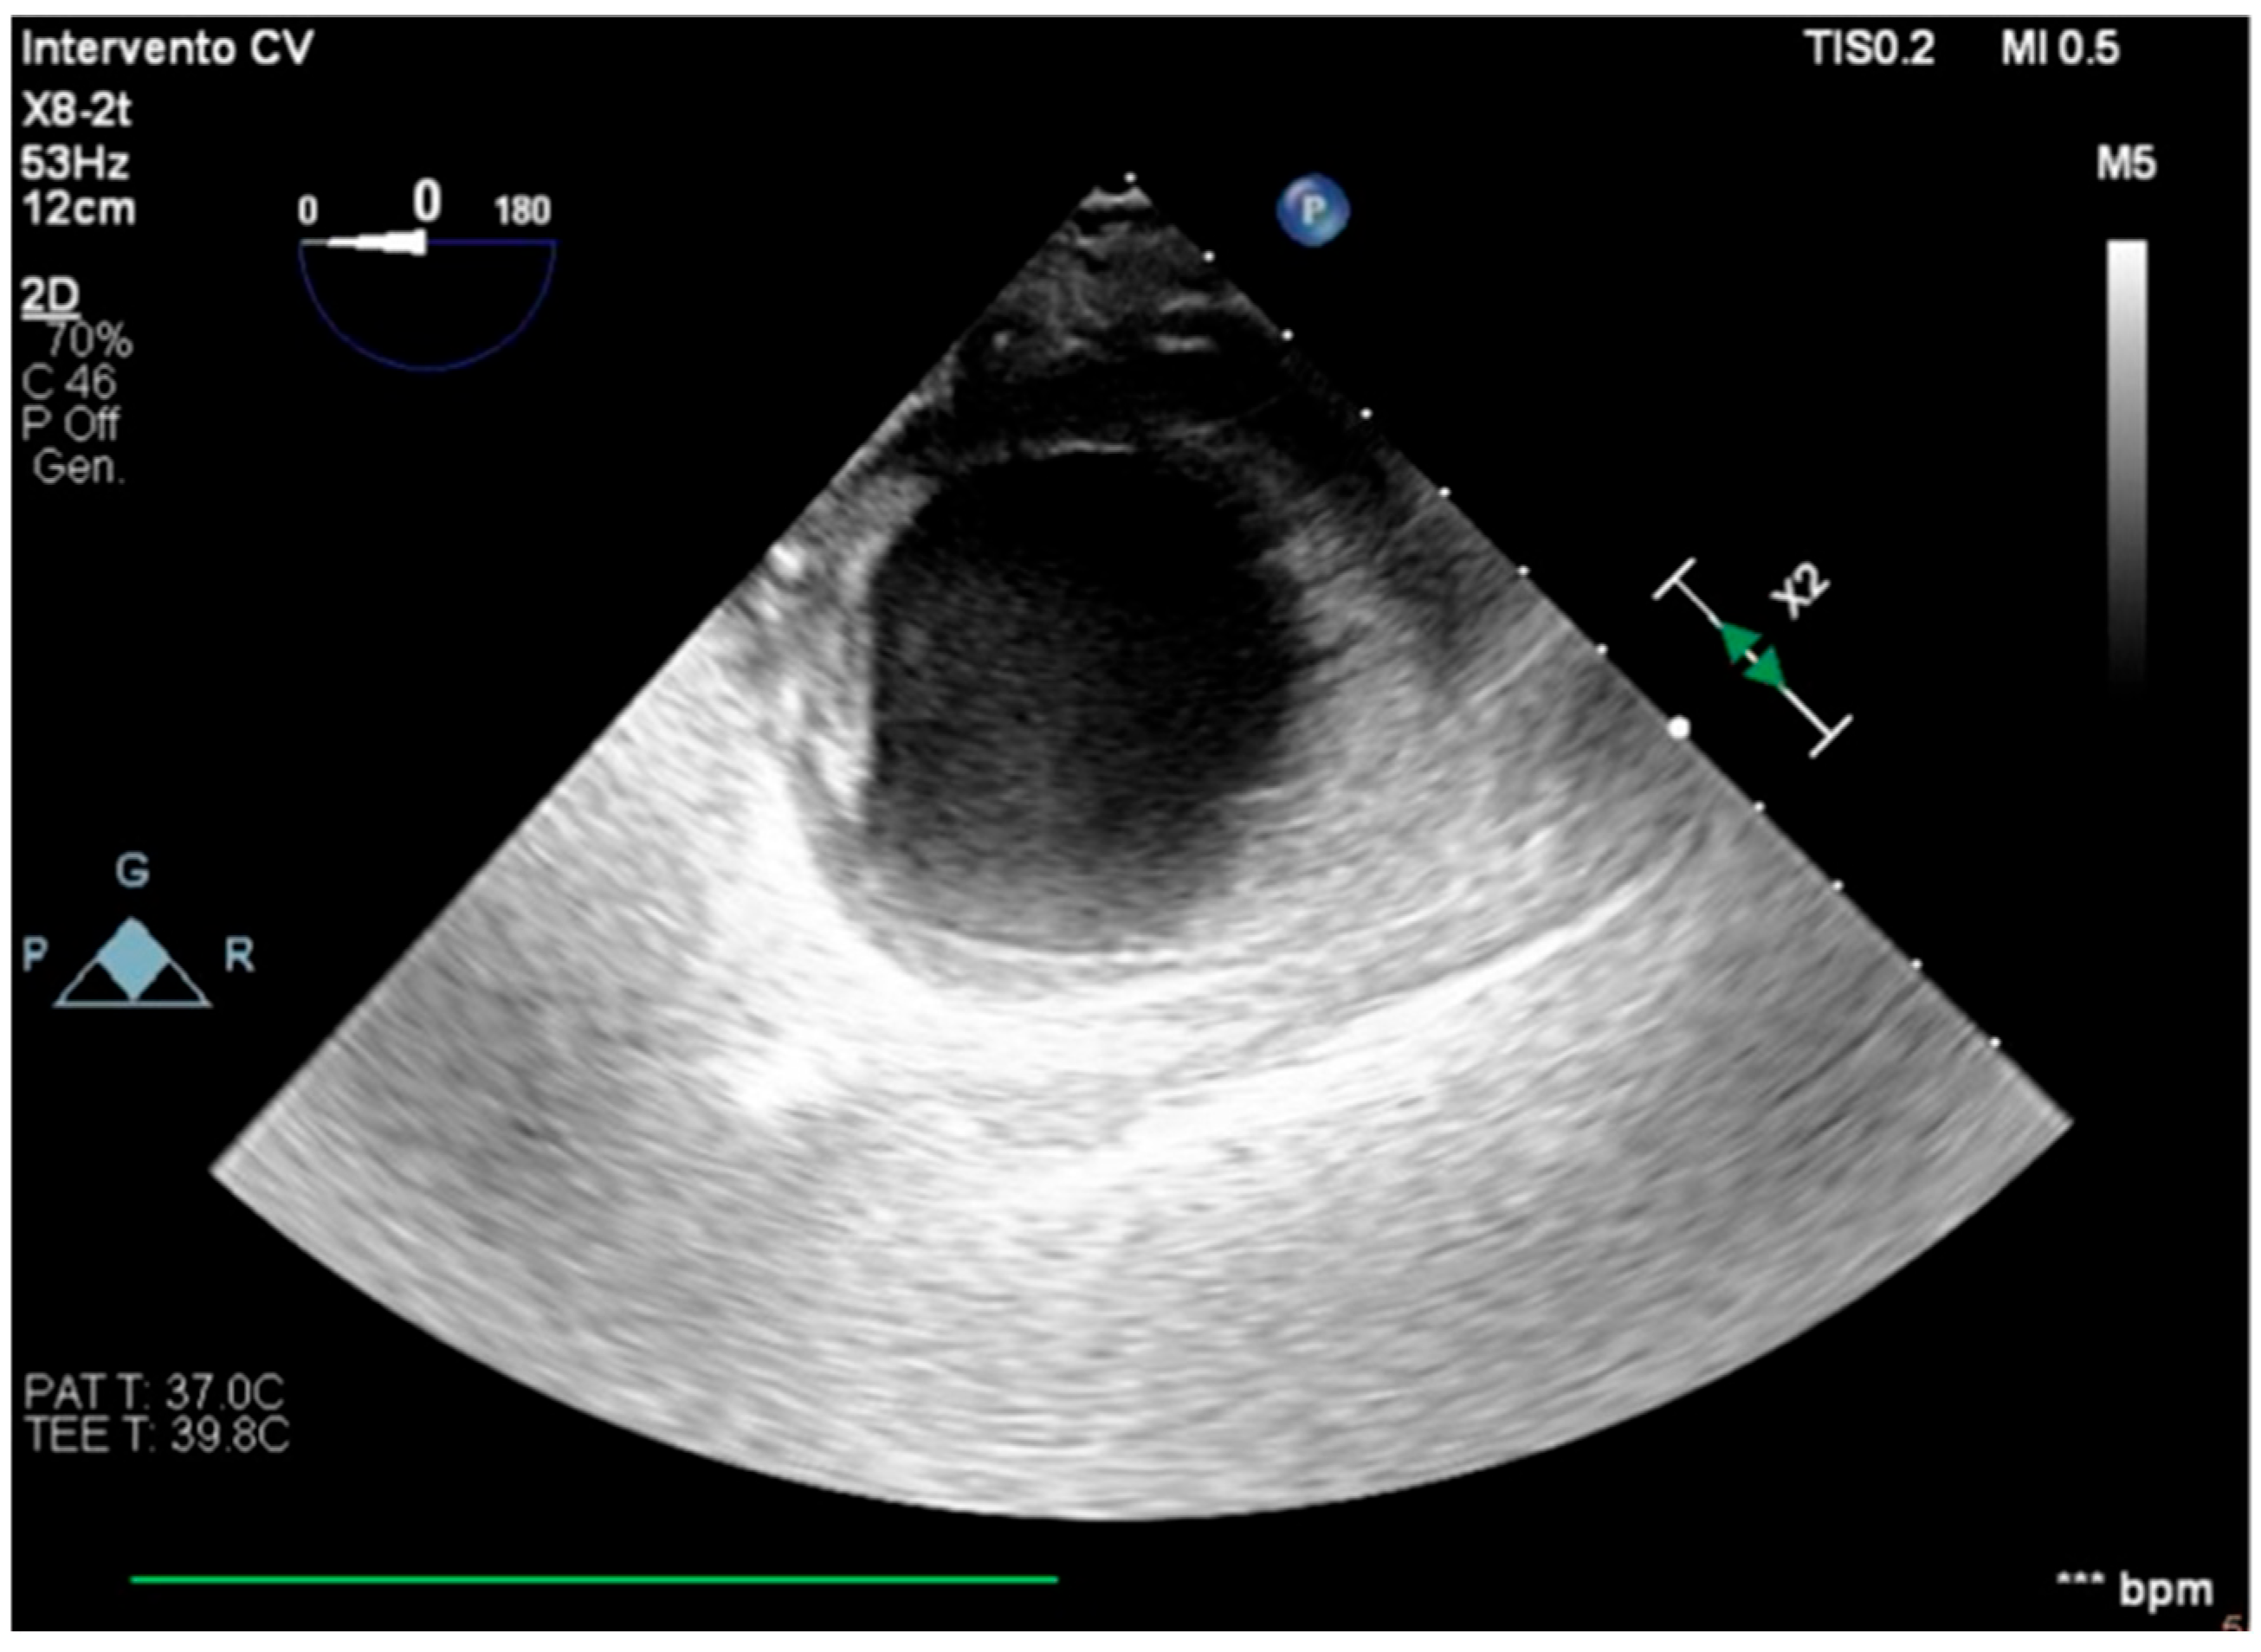

We describe a case of a 75-year-old woman affected by a post-myocardial-infarction ventricular septal defect (VSD) and a left-ventricle (LV) apical aneurysm. The patient underwent surgery for VSD closure and aneurysm exclusion. The patient had a STEMI (ST-elevation myocardial infarction), with evidence of occlusion of the anterior interventricular artery, for which thrombus aspiration and stenting of the left coronary artery and proximal anterior interventricular artery was performed. Then, she developed cardiogenic shock with pulmonary edema and thus required the support of an IABP (intra-aortic balloon pump) of C-PAP and levosimendan in continuous infusion for 24 h. Seven days after the event, a large post-infarct VSD at the apical level with a left–right shunt occurred. She was therefore transported from the spoke center to our hospital and underwent surgical treatment, namely, post-infarct VSD closure and exclusion of a left ventricular aneurysm. The intra-operative transesophageal echocardiography showed concentric LV remodeling, slight dilatation, LVEF 28% (Figure 1), and akinesia of the mid-apical segments in toto with aneurysmal evolution (Figure 2).

Figure 2. Trans-gastric view, apical level (short axis).